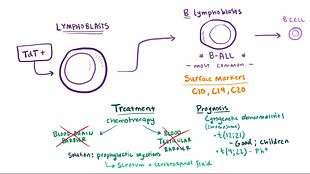

The malignant cell in AML is the myeloblast. In normal hematopoiesis, the myeloblast is an immature precursor of myeloid white blood cells; a normal myeloblast will gradually mature into a mature white blood cell. In AML, though, a single myeloblast accumulates genetic changes which "freeze" the cell in its immature state and prevent differentiation.[30] Such a mutation alone does not cause leukemia; however, when such a "differentiation arrest" is combined with other mutations which disrupt genes controlling proliferation, the result is the uncontrolled growth of an immature clone of cells, leading to the clinical entity of AML.[31]

Much of the diversity and heterogeneity of AML is because leukemic transformation can occur at a number of different steps along the differentiation pathway.[32] Modern classification schemes for AML recognize the characteristics and behavior of the leukemic cell (and the leukemia) may depend on the stage at which differentiation was halted.

Specific cytogenetic abnormalities can be found in many people with AML; the types of chromosomal abnormalities often have prognostic significance.[33] The chromosomal translocations encode abnormal fusion proteins, usually transcription factors whose altered properties may cause the "differentiation arrest".[34] For example, in acute promyelocytic leukemia, the t(15;17) translocation produces a PML-RARα fusion protein which binds to the retinoic acid receptor element in the promoters of several myeloid-specific genes and inhibits myeloid differentiation.[35]